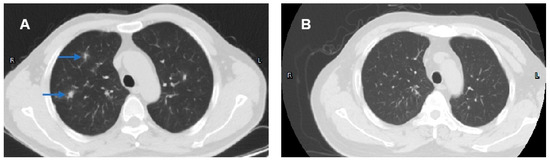

| 25 (ours) | M | 44 | Yes | Sjogren’s syndrome, tubulointerstitial nephritis, interstitial lung disease | 5-ASA, CS, IFX, UST | UDCA | |